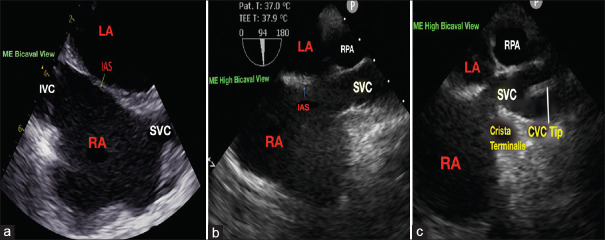

Background and aims: The main aim of this study was to evaluate the efficacy of real-time intraoperative transesophageal echocardiography (TEE) in guiding the central venous catheter (CVC) tip placement at the superior vena cava (SVC)-right pulmonary artery (RPA) junction.

Materials and methods: One hundred patients aged between 18 and 65 years undergoing elective cardiac surgery were enrolled in the study. In the operation room, under ultrasound guidance, right internal jugular vein was punctured and CVC was inserted. The primary outcome was to determine the accuracy of placing the CVC tip under TEE guidance at the SVC-RPA junction by intraoperative surgical palpation and to correlate between the preoperative chest radiograph-predicted CVC depth and the TEE-guided placement of CVC depth. The secondary outcomes were to evaluate the position of CVC tip in relation to the carina in postoperative chest radiograph and the incidence of complications.

Results: A total of 98 patients were included in the analysis. The CVC tip was palpable by the surgeon intraoperatively at the SVC-RPA junction in 76 patients (77.6%). A significant direct correlation was observed between the predicted preoperative CVC depth and TEE-guided placement of CVC depth (r = 0.7441, P < 0.0001). In the postoperative chest radiograph, 78 (79.5%) patients had the CVC tip positioned above the carina. Twenty-nine patients had atrial ectopics and six patients had ventricular ectopics during CVC insertion.

Conclusions: TEE-guided SVC-RPA junction is an accurate landmark for the intraoperative positioning of CVC tip in the extra-pericardial portion of SVC to prevent life-threatening cardiac complications.